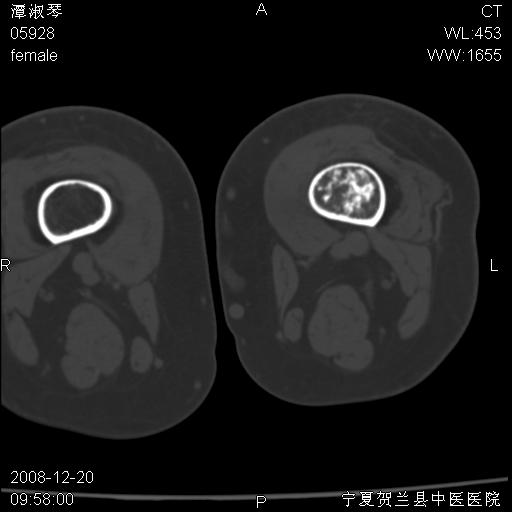

标题: CT17526:请各位看看是啥?

内生软骨瘤?骨梗死?

考虑内生软骨瘤可能性大

考虑-----骨梗死+退变

支持骨梗死,退行性骨关节病,膝关节积液.

考虑骨梗死可能性大

骨梗死可能性大

左股骨下段骨梗死。双膝退变。

左胫骨下端松质骨及髓腔内可见点片状高密度灶,骨皮质无明显膨胀及变薄。病变范围较长。支持骨梗死,退行性骨关节病,膝关节积液